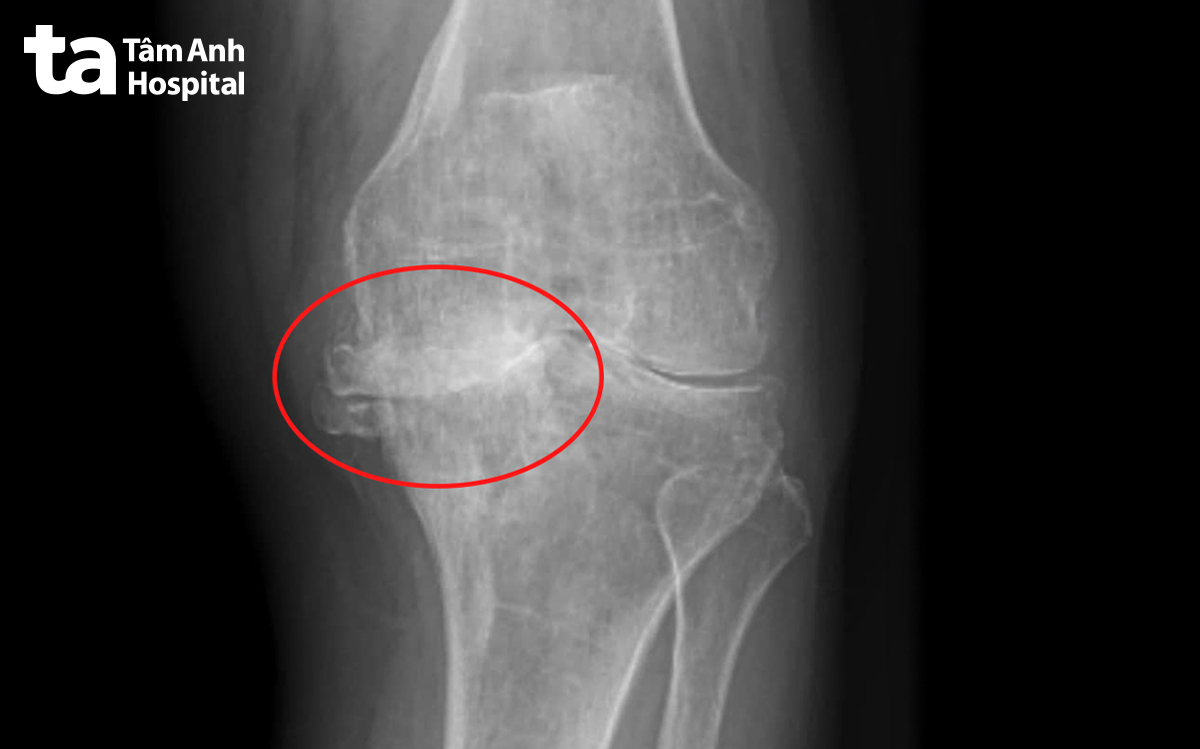

Kết quả chụp X-quang cho thấy khớp gối trái của người bệnh đã bị thoái hóa giai đoạn cuối trên nền viêm khớp dạng thấp, biến dạng nặng, vẹo trục 15 độ, mất hết sụn, tổn thương xương dưới sụn, mất xương mâm chày bên trong. Người bệnh còn bị suy giảm chức năng gan thận, dẫn đến bệnh thận mạn giai đoạn sớm do tự ý dùng nhiều thuốc trong thời gian dài.